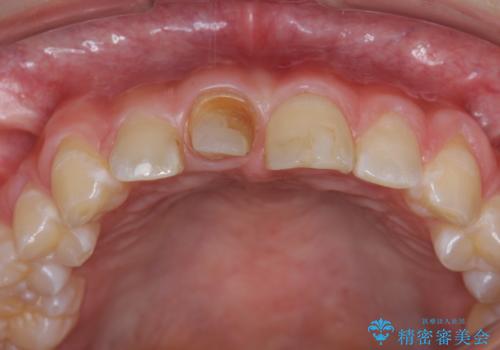

前歯をきれいにしたい ジルコニアクラウンによる審美治療

- 前歯の見た目の改善を求めて来院されました。

ジルコニアクラウンによる審美性の改善を計画します。

失活歯のため捻転を改善し、根管治療は特に希望されなかったのでそのままとしました。

今回失活歯であったため捻転を取り反対側の前歯に揃えて補綴を行うことができました。